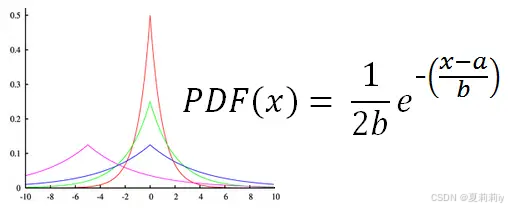

⑤Laplace Mechanism: 我先随便插几张拉普拉斯分布的图,可以见得它和高斯分布有点类似只是是尖尖的,而且也是俩参数,公式还比高斯看起来简单一点:

They employ Laplace Distribution with scale :

and , the

noise will be add to

, the difference privacy is

(作者只用了一个参数咩~)。然后他们为了简化讨论假定灵敏度

为1???这能假定吗?这不是两个数据集间的差异吗。我猜测作者是在说两个站点间参数的差异为1?